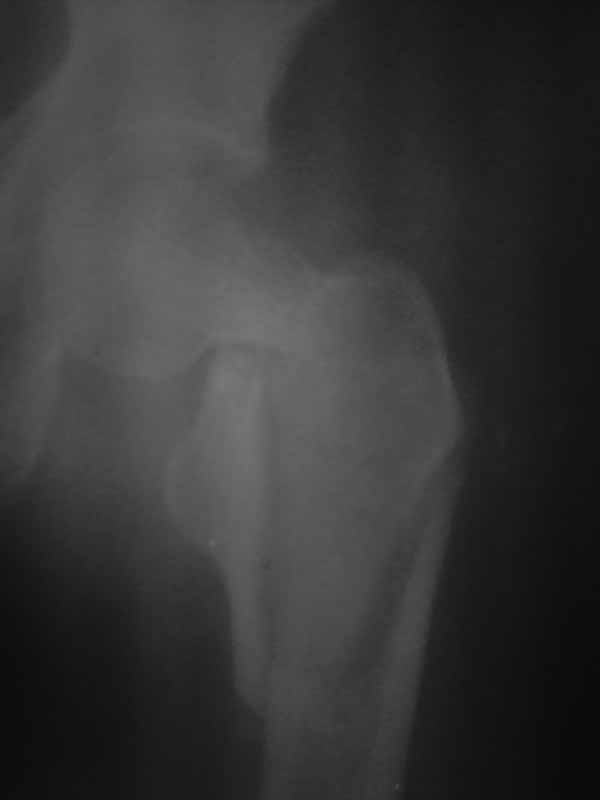

Re: перелом шейки бедра

Снимок, конечно, паршивый - лучше было повременить с размещением вопроса до возможности сопроводить его нормального качества иллюстрациями.

как расшифровывается DXS?

Перелом идет на диафиз, так что если придется использовать пластину, то надо длинную, да с угловой стабильностью - клинковую, может.

Тут, видимо, лучше использовать реконструкционный гвоздь - не знаю, какова на месте степень недоступности такого типа имплантатов. Где вы находитесь? Может, попытаться прислать подходящую железку?

Немало доводится лечить пациентов с несостоятельной фиксацией подобных переломов всякими случайными пластинами и винтами.

Хотелось услышать дискуссию, по-этому выложил некачественный снимок с вопросом. Стараюсь выложить немного лучше. Гамму она приобрести не сможет. Смущает то что шейка больно хлипкая и винтом развалим ее до конца. На снимке кажется что и фрагмент шейки также сломан вдоль.